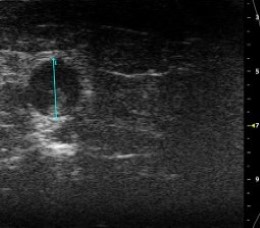

- in vivo VisualSonics Vivo 2100 vascular imaging

Abdominal Echo's performed 24 hours prior to sac using VisualSonics Vivo 2100